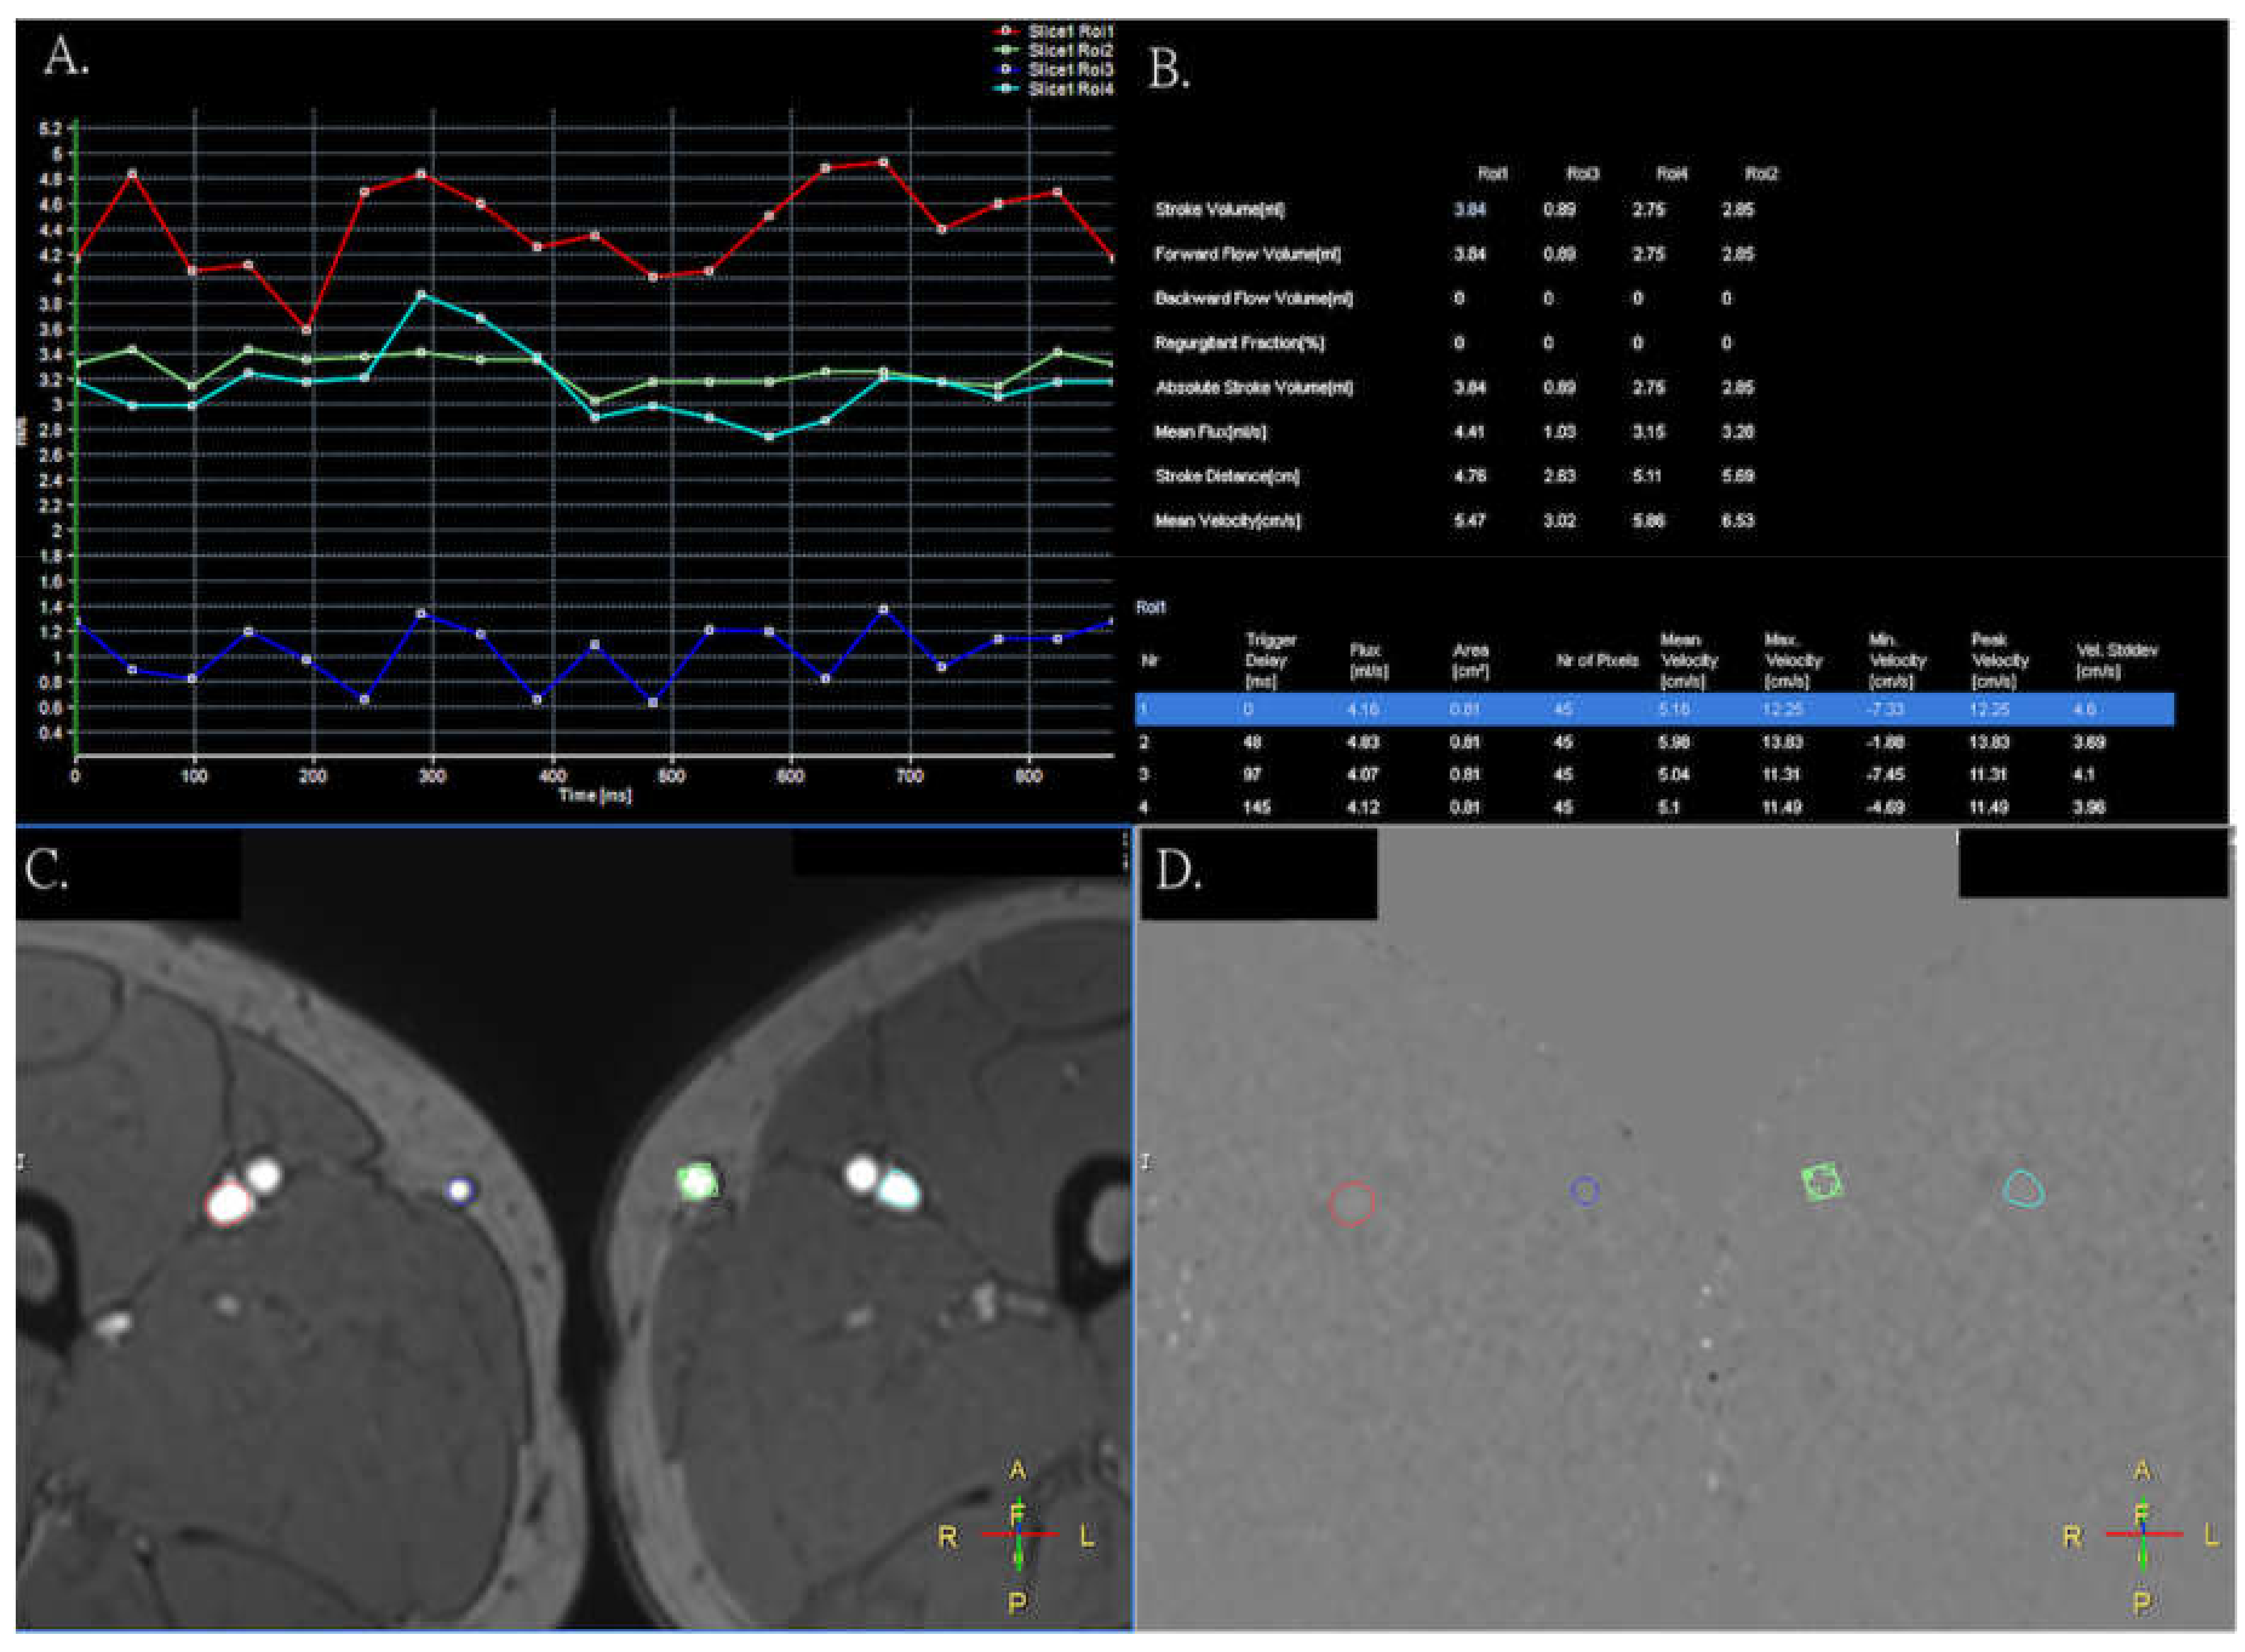

2. Methods

2.2. MRI Acquisition

3. Results

4. Discussion